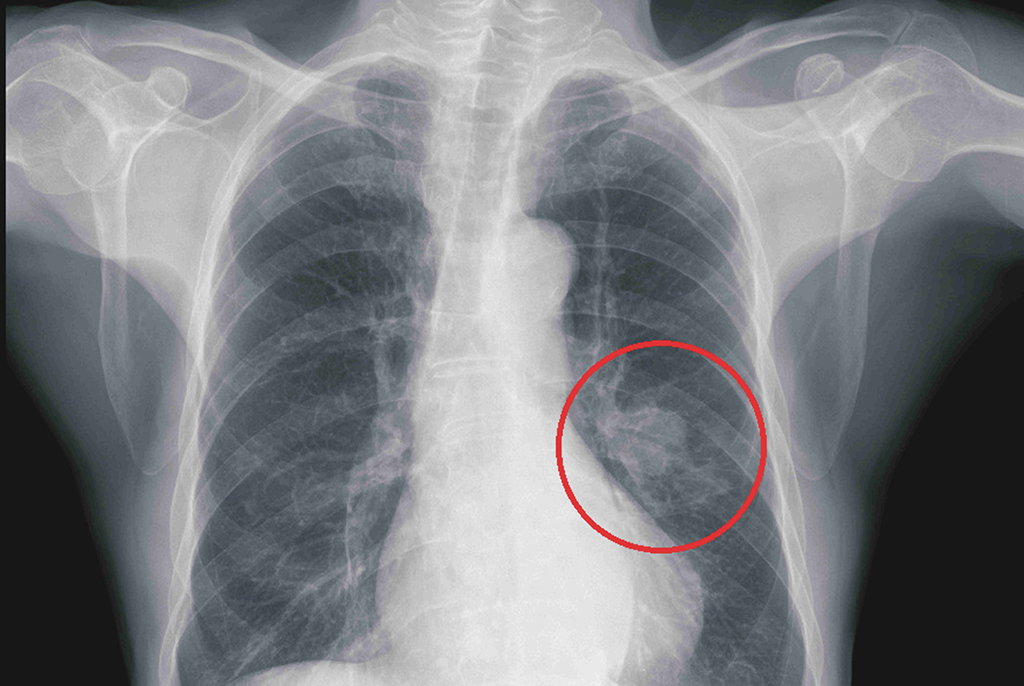

鄭雅夫醫師指出,一位52歲男性為因為罹患下咽癌合併多處轉移,經過化療及免疫治療後,仍然有右上肺及右下肺的腫瘤存在。患者於7個月前接受胸腔鏡右上肺及右下肺部分切除後腫瘤控制較穩定。此次再次發現右下肺長出一顆三公分的腫瘤,有鑑於病患的肺功能不佳,二次手術也容易沾黏較不合適,於是選擇了在複合式手術室中做微波肺部消融術治療,術後腫瘤消融狀況良好,病患也於觀察一天後即可出院,肺部消融術是一項針對不適合接受肺部切除術的良好替代選擇。

52歲男性患者,微波消融術前,右下肺一顆3公分腫瘤。

52歲男性患者,腫瘤經微波消融術而壞死。